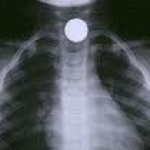

The presence of foreign bodies in the lungs can present with long term symptoms such as asthma and cough. Chest X ray will show collapse on the affected side.

Note the “white out” on the left due to collapse of the lung